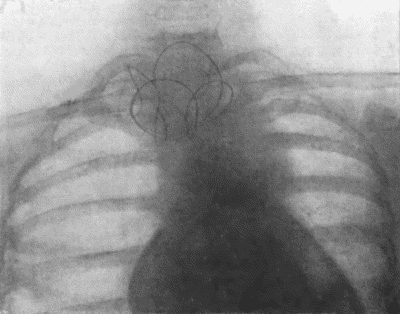

| 73. | Radiogram of Innominate Aneurysm after Treatment by Moore-Corradi method | 309 |

| 74. | Thoracic Aneurysm threatening to rupture | 313 |